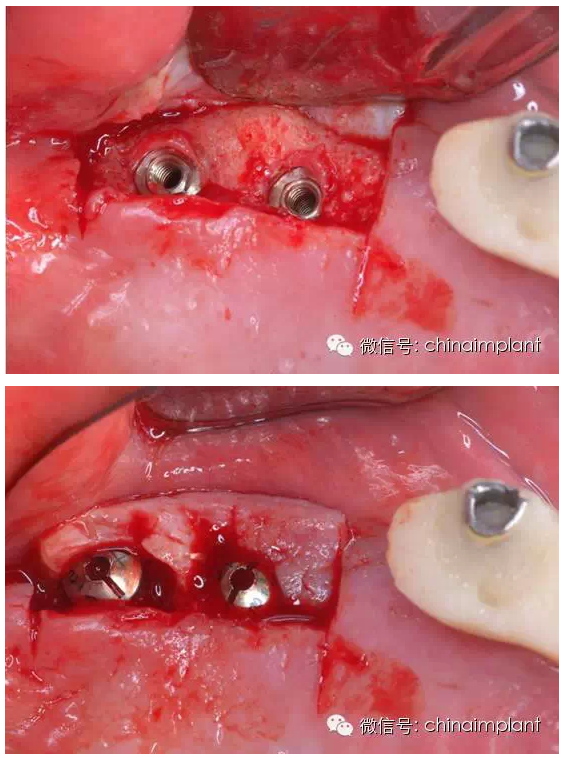

之前針對(duì)全口無(wú)牙進(jìn)行種植修復(fù)的案例中,因?yàn)轭M骨的原因,后期使用橋冠修復(fù)時(shí),一般是3部分(兩側(cè),磨牙,前牙),最近的案例中修復(fù)是一般都是做一體式的橋冠,現(xiàn)在從臨床的修復(fù)案例來(lái)看,沒有什么問(wèn)題。

之前的時(shí)候,使用圓錐形基臺(tái),但是附著的力量容易分散。(最近由于費(fèi)用的問(wèn)題多使用UCLA形態(tài)的基臺(tái))

此案例為術(shù)后兩周戴臨時(shí)牙。過(guò)去因?yàn)閾?dān)心感染的問(wèn)題,一個(gè)月以內(nèi)帶臨時(shí)牙也叫做即刻負(fù)重或者早期負(fù)重。(現(xiàn)在當(dāng)天戴臨時(shí)牙(即刻復(fù)重)的情況也非常常見).